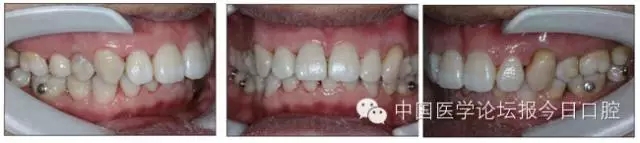

口內情況:恒牙列,24、34、44缺失,磨牙Ⅲ類關系,上牙列散隙,上前牙扇形漂移。前牙深覆(牙合)、深覆蓋。口腔衛(wèi)生較差,11與12間牙齦乳頭紅腫,多個牙探診有牙周袋形成,11松動Ⅰ度,余切牙松動(-),患者面像及口內像如圖1、2所示。

圖2 治療前口內像